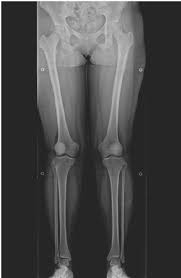

정상적인 다리 정렬에서는 체중이 무릎 중앙에 균등하게 분포되며, 관절에 가해지는 압력이 일정하다. 하지만 비정상적인 정렬, 즉 O자형(내반슬)이나 X자형(외반슬) 다리는 무릎 관절의 특정 부위에 과도한 압력을 가하게 된다. 이러한 압력 불균형이 장기간 지속되면 관절 연골이 점진적으로 마모되면서 관절염이 발생할 가능성이 높아진다.

2.2 O자형 다리와 관절염

O자형 다리(내반슬)는 무릎 관절의 내측(안쪽)에 더 많은 부담을 주는 형태로, 이로 인해 내측 연골이 빠르게 닳고 관절염이 심화될 가능성이 크다. 연구에 따르면 O자형 다리를 가진 사람은 정상적인 정렬을 가진 사람보다 무릎 관절염 발병률이 높으며, 관절염이 진행됨에 따라 다리의 변형이 더욱 심해지는 경향을 보인다. 이는 관절염으로 인한 연골 손실이 무릎의 특정 부위에서 더욱 집중적으로 발생하기 때문이다.